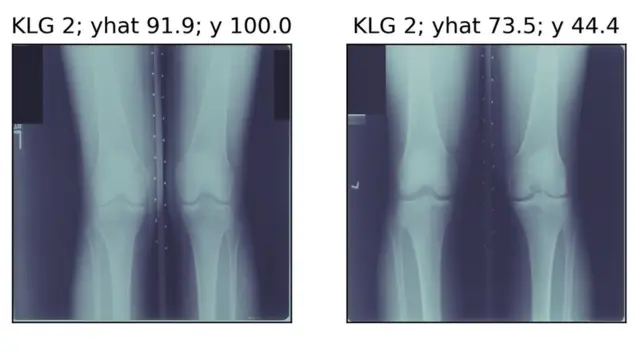

이런 차이점에 관한 연구 보고서가 최근 네이처 메디신지에 발간됐다. 연구진은 무릎 골관절염 환자가 겪는 통증을 예측하기 위해 인공지능 기술로 엑스레이 사진을 분석했다. 환자 4172명의 엑스레이 사진 3만6369개를 대상으로 했다.

이런 컴퓨터 분석을 통해 방사선 전문의들이 놓칠 수 있던 것을 잡아낼 수 있게 됐다. 버클리 대학의 조교수 이자 이번 보고서의 공동 저자인 지아드 오버마이어 박사는 "의사가 엑스레이를 보고 무엇을 말할지를 예측하기 위해 알고리즘을 설계하진 않았다"라고 연구 목적을 설명했다. 그는 "환자가 자신의 무릎 통증에 대해 어떤 말을 할지를 예측하기 위해 알고리즘을 설계했다."라고 덧붙였다.

이번 연구는 "흑인 환자들이 왜 더 심한 통증을 가졌는지", 그 '미스터리'를 탐구하는 것이 목적이다. 연구진은 방사선과 의사들이 보기에 통증 정도가 비슷한 관절염 환자를 검사해보니 흑인이 백인보다 더 심한 통증을 호소한다는 걸 밝혀냈다. 즉 알고리즘이 비슷해 보이는 사례가 생각보다 덜 비슷하다는 것을 확인한 셈이다. 이는 일반적으로 사용되는 방사선 평가 시스템으로 봤을 땐 간과할 수 있는 증상을 인공지능이 추가로 발견면서다.알고리즘과 환자 본인의 진단으론 통증이 심한 거로 인식되지만, 전통적인 방식으로는 통증이 낫은 거로 집계되는 집단이 흑인들이었다. 즉 전통적인 진단 방식은 흑인 환자에겐 적합지 않을 수 있다는 거다.

오버마이어 박사는 "알고리즘이 모든 이의 통증을 더 잘 설명 한다는 것을 발견했고 또한 모든 환자의 무릎 통증도 더 잘 찾아냈는데 이점은 특히 흑인 환자에게 큰 도움이 됐다"고 설명했다. 이런 발견은 특히 사회 경제적 지위가 낮고 저학력인 환자들과 영어를 모국어로 사용하지 않는 사람들에게도 유용하다.

하지만 연구진은 이번 연구에 중요한 한계점도 있다고 인정했다. '블랙박스'처럼 작동하는 딥 러닝의 특성상 엑스레이 사진에 나타난 병의 어떤 특징을 AI가 집어냈는지는 알 수 없다. 따라서 전에는 몰랐으나 인공지능이 감지한 통증을 앓는 환자들이 수술을 시키는 게 효과적인지 또한 미지수다.